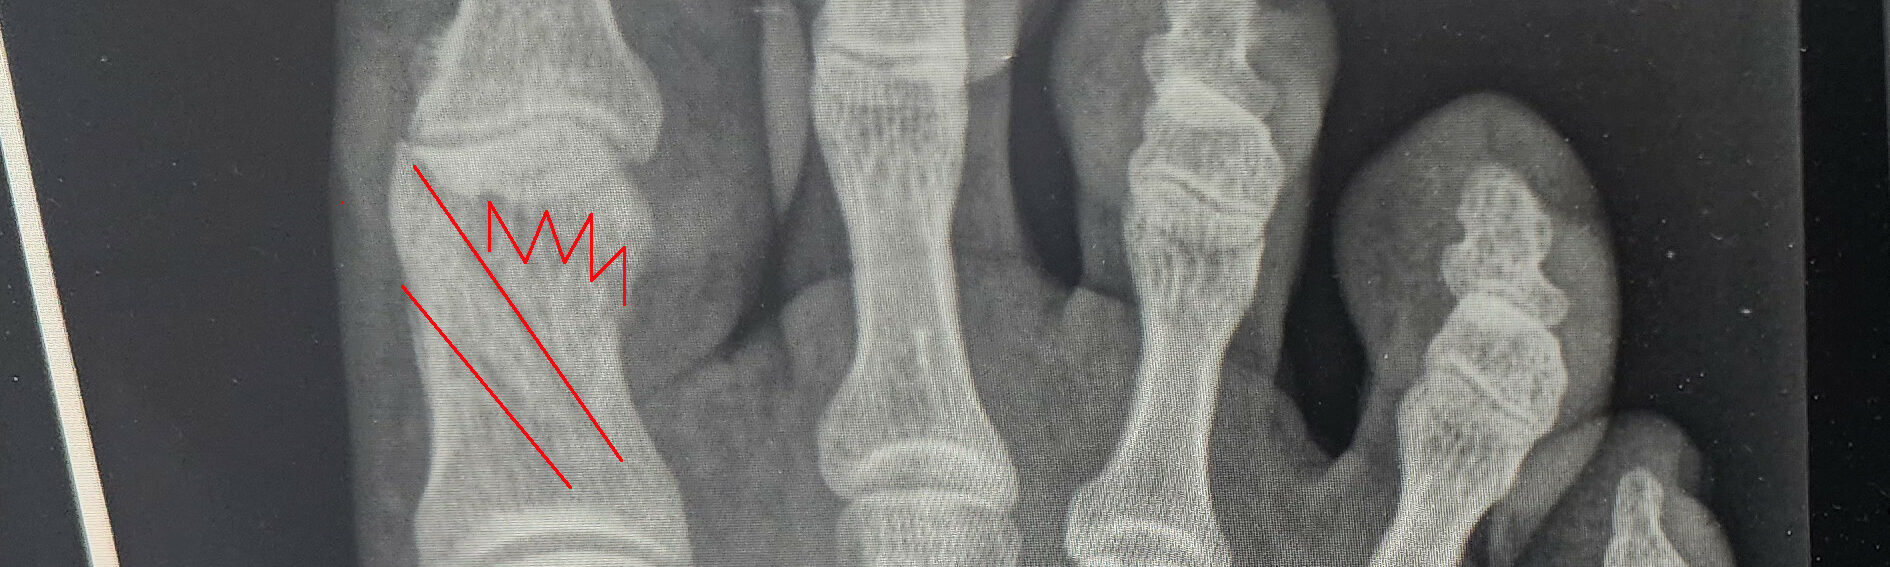

The doctor saw me at 9 am promptly. He immediately takes X-rays, and after a few minutes, I hear from the other room, ‘NICE’! It is never good when a doctor says that. The aftermath was four fractures in the right big toe in an x pattern. My Wolverine-esque, aka big bones, is why things barely held together instead of completely shattering. I would have a 6-8 week recovery period before I could start using the toe again. Effectively, pressing pause on my race season.